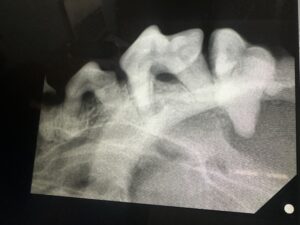

① 麻酔下の歯石除去(スケーリング)

適応範囲:術前検査費用+歯石除去。それ以外の診察料や抜歯、歯科レントゲンなどが必要な場合は別途となります。

歯垢(プラーク)はたった3日で歯石に変わります。歯石はただの汚れではなく、細菌やミネラルのかたまり。

そのままにしておくと、歯周病や、時には全身の感染症にまでつながってしまうこともあります。歯垢のうちなら歯みがきで落とせますが、一度歯石になると、もう歯みがきでは取れません。

※処置中には、問題のある歯の抜歯や、のどの奥や粘膜の腫瘍などのチェックも行います。